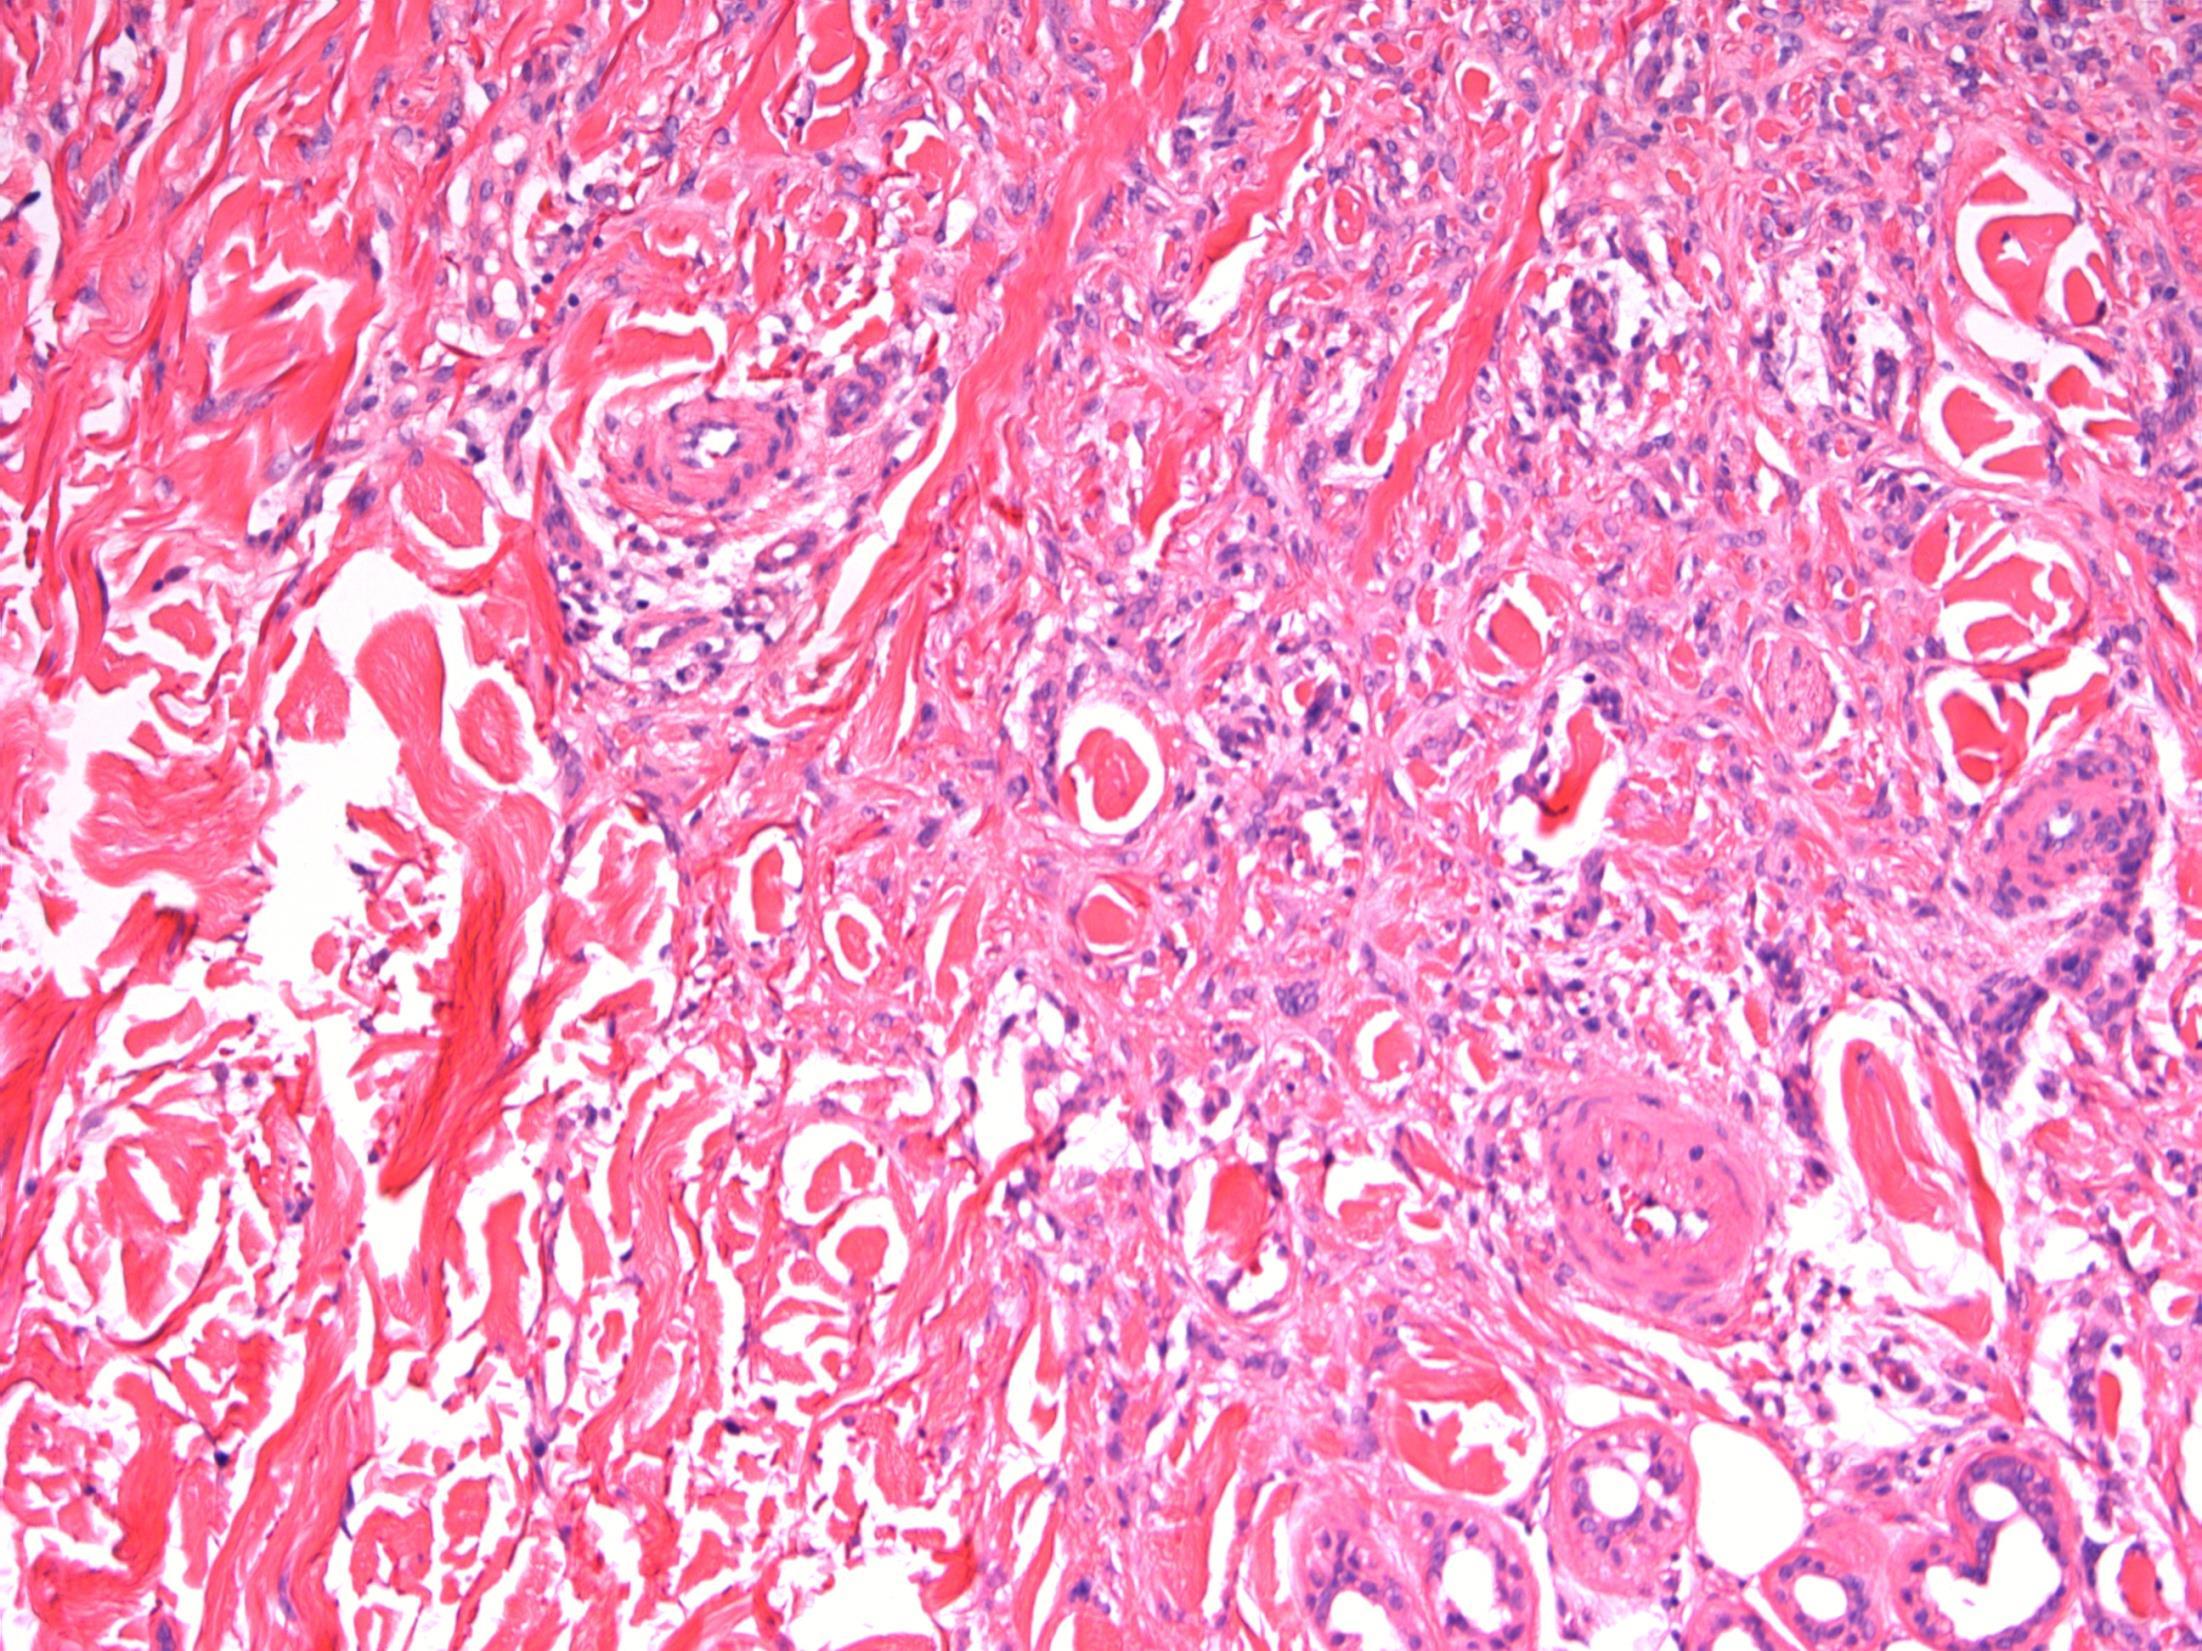

TURBT - G3 (high-grade) TCC with small cell carcinoma component

AE1/3 - TCC AE1/3 – small cell CD56 - TCC CD56 – small cell

cell

- TCC

P63 - TCC

Synapto

small

P63

small cell

G3 (high-grade) TCC with small cell carcinoma component

Description: Biphasic malignant tumour. High grade large epithelial cell component and high grade small round blue cell tumour component. CIS also seen.

Favoured Diagnosis: G3 (high-grade) TCC with small cell carcinoma component. Plan: Correlate with urine cytology/ previous biopsies. IHC: TCC= AE1/3+, p63+, small cell ca = AE1/3 dot +, CD56+, synapto +. Look for invasion into lamina propria and muscle (staging).

Comments: • Small cell carcinoma is frequently admixed with TCC, SCC or adenocarcinoma of bladder • >90% muscle invasive and metastases common, poor prognosis. • Responds to chemotherapy (cisplatin based) • Differential Diagnosis of pure small cell carcinoma: – Poorly-differentiated urothelial carcinoma – Metastatic small cell carcinoma from other site eg lung – Lymphoma – Alveolar rhabdomyosarcoma – Inflammation (in a crushed, cauterised, superficial or scant specimen)